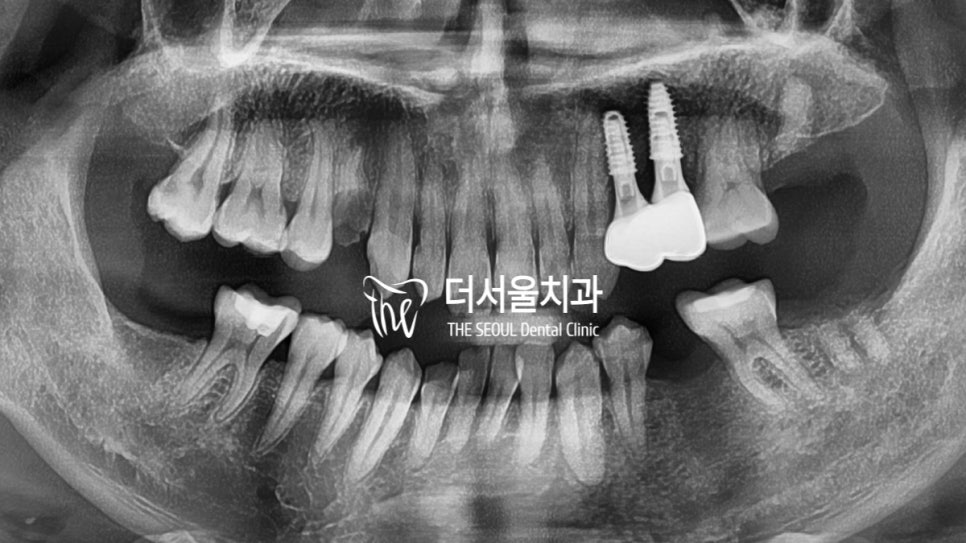

몇 달 뒤 골유착이 완료된 이후

최종 크라운 결합을 도와드렸습니다.

잔존 치근이 새하얀 지르코니아 크라운으로

바뀌어 있는 모습을 볼 수 있는데요.